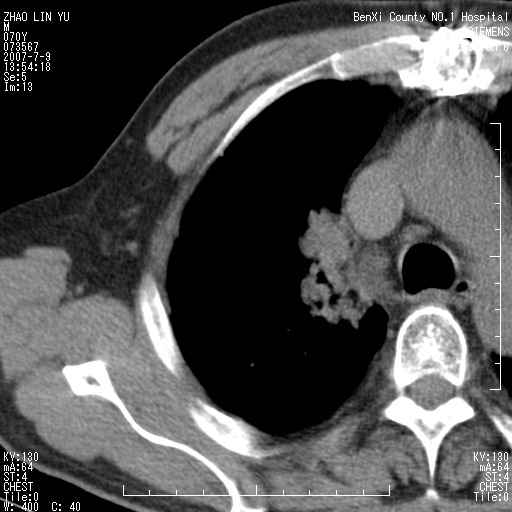

以下是引用王靖旗在2007-7-10 17:12:00的发言:[br] 男、70、咳嗽两个月,半年前换瓣手术,胸片未见异常,于昨天行x片发现右肺上野大片影,行ct扫描,这里是减薄图像,余肺正常。明天晚上会有增强扫描片,到时我会上传。[br][br] 冠状位请大家细看,应该是有意义的,[br][br] 请大家先看平扫发表意见。[br][br]

以下是引用zhangzhongshou在2007-7-10 21:43:00的发言:[br]右肺上叶周围型肺癌,以孤立型细支气管肺泡癌可能性大。